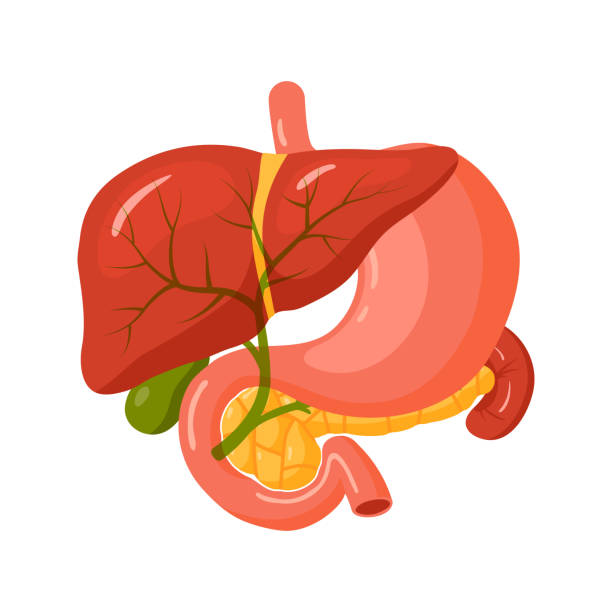

Biliary Interventions